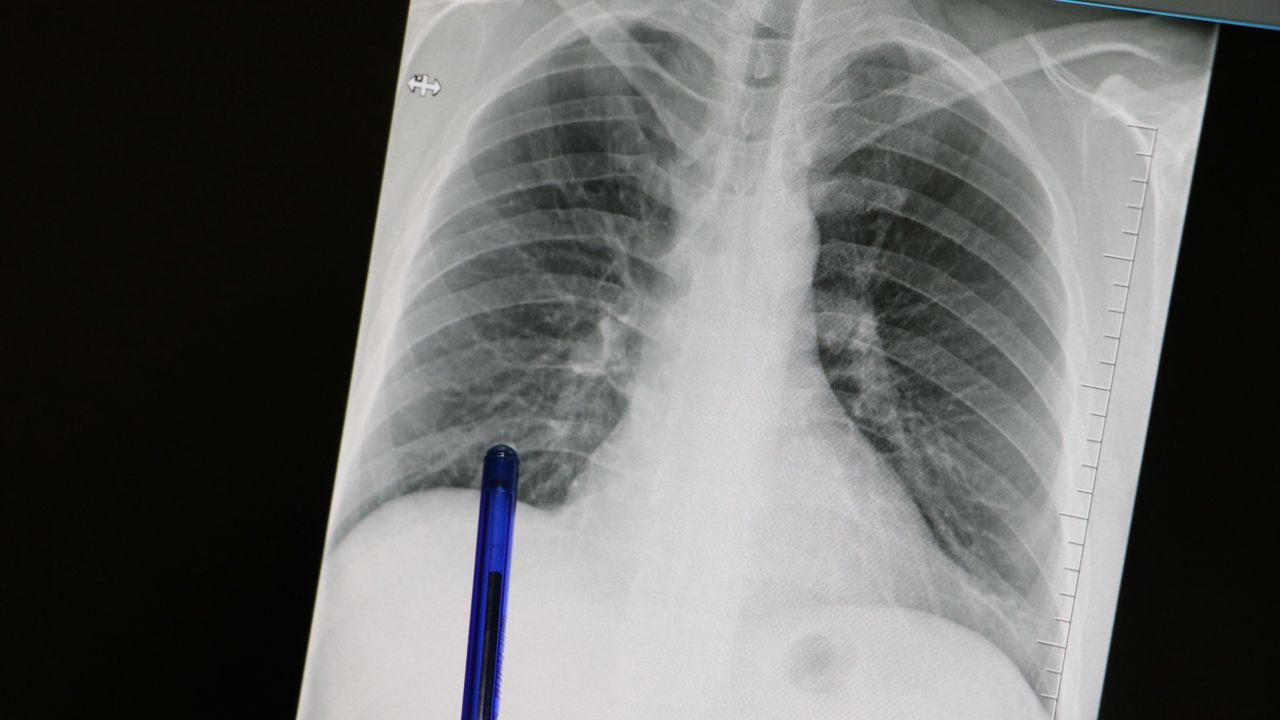

Kasım ayı, Türkiye’de akciğer kanserine dikkat çekmek ve erken tanının önemini vurgulamak amacıyla ‘Akciğer Kanseri Farkındalık Ayı’ olarak kabul ediliyor. Akciğer kanseri, akciğer dokusundaki hücrelerin kontrolsüz şekilde çoğalmasıyla ortaya çıkan ve diğer organlara yayılabilen ciddi bir hastalık olarak biliniyor. Genellikle erken evrede belirti vermemesi nedeniyle çoğu zaman geç fark ediliyor ve tedavi şansını azaltıyor.

Medicana Sivas Hastanesi Göğüs Hastalıkları Uzmanı Dr. Büşra Yayla Yerlikaya, öksürük ve balgam çıkarma gibi basit görünen belirtilerin akciğer kanserinin işareti olabileceğini belirterek, erken tanının önemine dikkat çekti.

"Akciğer kanserinin en sık belirtileri ise uzun süren öksürük, balgamda kan, nefes darlığı, kilo kaybı ve göğüs ağrısıdır. Özellikle sigara içen birinde yeni başlayan ya da karakteri değişen öksürük varsa mutlaka bir göğüs hastalıkları uzmanı tarafından değerlendirilmelidir. Erken tanı her kanser türünde olduğu gibi akciğer kanserinde de hayat kurtarır. 50 yaş üzeri ve uzun süre özellikle 20 paket yıl ve daha fazla sigara içmiş kişilerde düşük doz tomografi ile tarama yapılması, hastalığın erken evrede erken tanı sağlar ve tedavi şansını ciddi şekilde artırır. Sigarayı bırakmak her yaşta faydalıdır. Bıraktıktan sonraki on yıl içinde akciğer kanseri riski büyük oranda azalır. Çalışmalar 10 yıl sonra yüzde 50, 15 yıl sonra ise yüzde 90'a kadar akciğer kanseri riskinin azaldığını göstermiştir. Sigara içen bireylerde sabahları balgam ve öksürükler mevcut oluyor. Bu durumlarda balgamın karakter değiştirmesi ve artması önemli bir belirti olabiliyor."